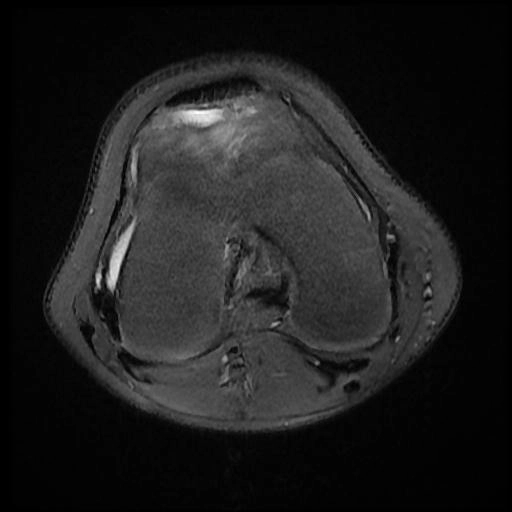

Nang sụn chêm (Meniscal cyst)